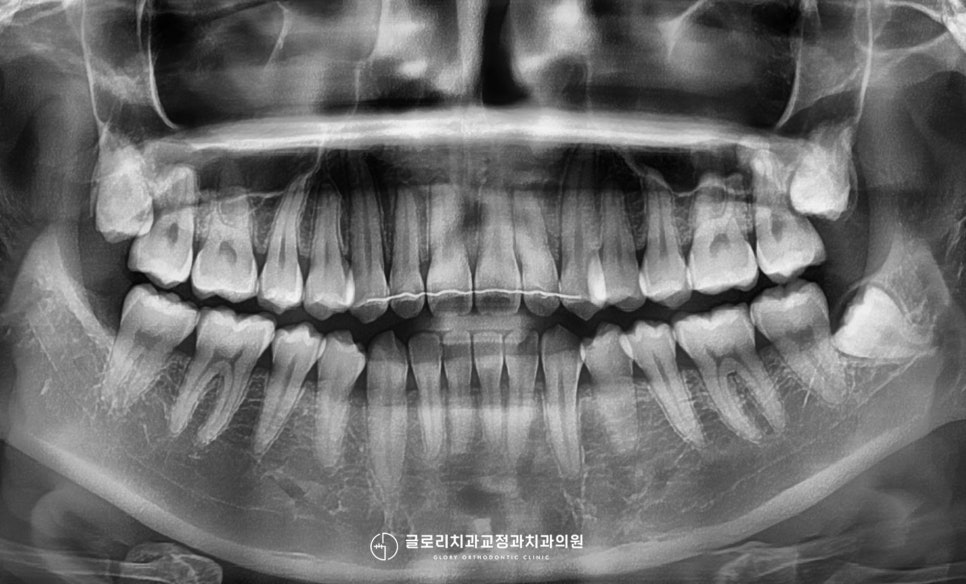

1. 초진

“위에 앞니 틀어짐이 딱 보여요.

이곳만 치료할 수는 없을까요?”

위의 주소로 저희 신내동 치과 를

찾아오신 20대 남성 환자의 증례를

소개해 드리겠습니다.

정면에서 구내를 보았을 때

위 전치부의 틀어짐이 관찰되는데요.

크게 회전된 양상은 아니었지만,

정중선이 일직선으로 맞지 않아

조금 눈에 띄는 정도였는데요.